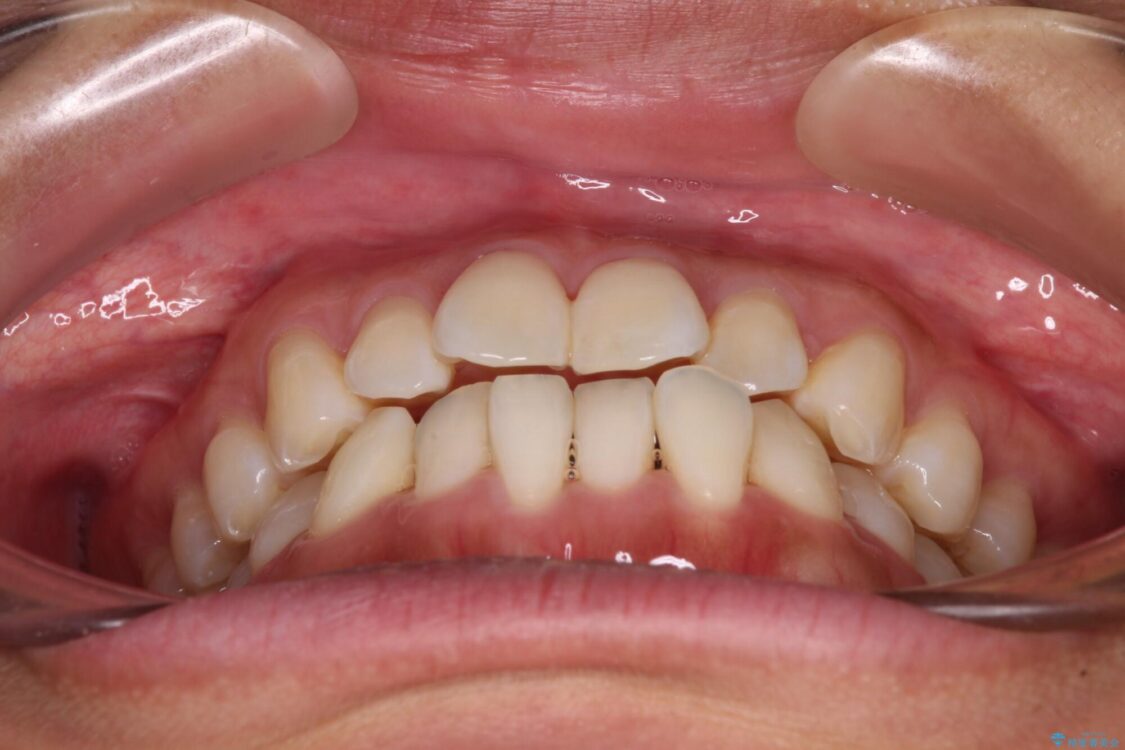

前歯のデコボコで前方に出ていることを気にして来院された患者様です。

上顎前歯が捻れて前方に飛び出しており、下顎前歯もそれに沿うようにデコボコとなっていました。

IPR(歯と歯の間を削る処置)によりスペースを獲得して上下顎前歯のデコボコを改善し、飛び出している前歯が引っ込むように設定し、インビザラインにて矯正治療を行うこととしました。

治療前

• 【モニター】前歯のデコボコをインビザラインで改善 治療前画像